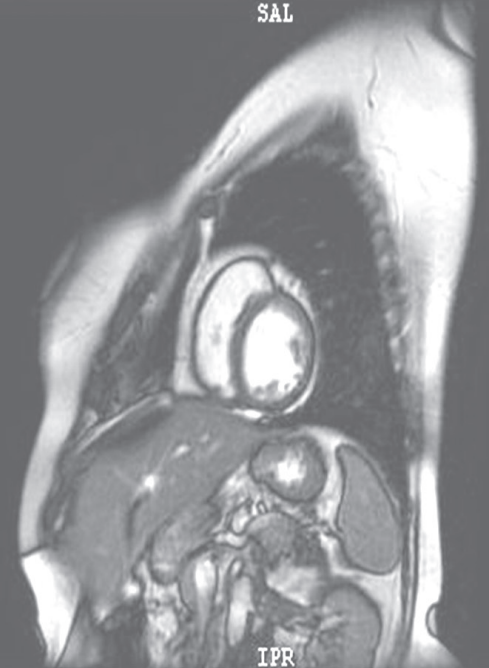

心脏MRI见心肌灌注均匀(图4)。

图4 心肌MRI结果